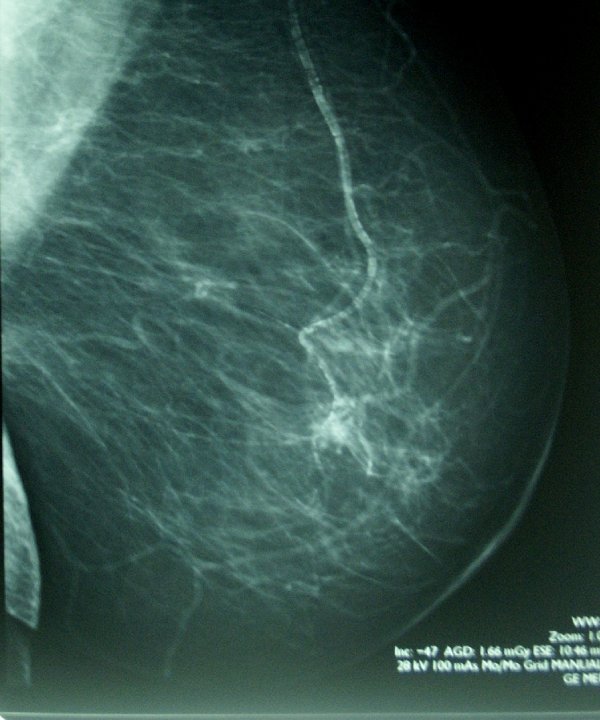

Švédská studie, provedená na 100 000 ženách, ukázala, že využití umělé inteligence při vyhodnocovaní snímků z mamografického screeningu, zvyšuje míru včasné detekce a zároveň snižuje počet diagnóz v letech následujících po vyšetření..

Jedná se o dosud největší studii zkoumající využití umělé inteligence při screeningu rakoviny. Bylo do ní zahrnuto 100 000 švédských žen, které se zúčastnily mamografického screeningu v období od dubna 2021 do prosince 2022, přičemž jejich snímky byly náhodně zařazeny buď do skupiny vyhodnocované umělou inteligenci, nebo standardním způsobem prováděným dvěma radiology.

AI přitom pracovala tak, že nízkorizikové snímky přiřazovala radiologům k jednomu čtení, zatímco podezřelé případy k dvojitému čtení.

Zároveň zvýrazňovala podezřelé nálezy, které měli radiologové posoudit. Ze závěrů výzkumu, publikovaných v časopise The Lancet vyplývá, že mamografické vyšetření, do něhož byla zapojená umělá inteligence, snížilo počet diagnóz v letech po absolvování screeningu o 12 % ve srovnání s kontrolní skupinou.

Ve skupině podporované AI bylo 1,55 případů rakoviny na 1000 žen ve srovnání s 1,76 případy na 1000 žen v kontrolní skupině.

Více než čtyři z pěti případů rakoviny (81 %) ve skupině s mamografií s využitím umělé inteligence byly detekovány ve fázi screeningu, ve srovnání s necelými třemi čtvrtinami (74 %) v kontrolní skupině, a ve skupině se zapojením umělé inteligence se rovněž objevilo téměř o třetinu (27 %) méně agresivních podtypů rakoviny ve srovnání s kontrolní skupinou.